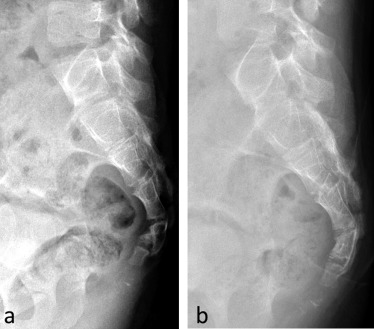

Рентгенографию выполняют в двух проекциях:

Прямая проекция. Пациент ложится на спину и сгибает ноги в коленях. При съемке крестца необходимо согнуть коленные и тазобедренные суставы. Если есть травма копчика, ноги остаются прямыми, а руки располагаются вдоль тела.

Боковая проекция. Пациент укладывается на бок и заводит руки за голову. Ноги сгибаются в коленях и прижимаются к животу. Для удобства под колени помещается валик. При рентгенографии крестцово-копчикового отдела исследование проводится в диагональных проекциях.

Рентгенографию копчика обычно проводят в двух проекциях, но в некоторых случаях их количество может быть увеличено.